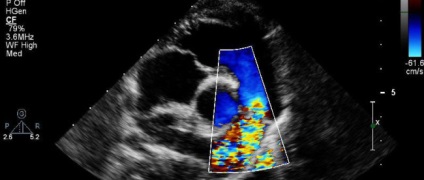

Color flow mapping

Tehát, az egyik alfaja a fő vizsgálat színleképezési alkalmazott ellenőrzés ugyanazt a hajót. A megjelenítő eszköz nem jelenik meg a fekete-fehér kép, és a különböző színárnyalatok, amelyek azt mutatják, egy képet a vér áramlását, a tájékozódás és érrendszeri lumen mérete és az ellenállás.

vaszkuláris Doppler (például képeket)